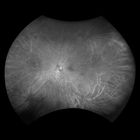

Daytona provides eyecare professionals with UWF digital images of 200 degrees or up to 82% of the retina in a single, non-contact optomap image. In addition, the Daytona device comes with the OptosAdvance™ browser-based image review software, which allows for simple documentation, monitoring and referral processing to assist in patient management and improved patient flow.

optomap has been shown to enhance pathology detection and disease management and to improve clinic flow. The Daytona system is the most widely used true UWF imaging device.